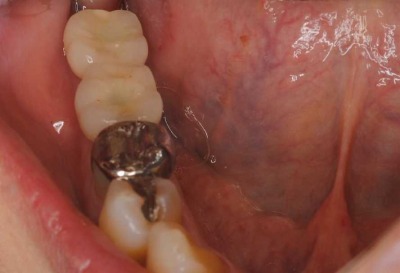

2012.04.28 院長ブログ インプラント3 今日のインプラントは、右下の奥歯に2本でした。本来なら入れ歯になる所ですが、入れなくて済んで良かったと感動されて帰りました。ゴールデンウィークに間に合ってよかったですね。 レントゲンで見るとインプラントから歯に移行する立ち上がりのラインもきれいに仕上がっています。 上の歯が少し伸びてきていて、歯の高さが十分に確保できず上からのネジ固定ですが、ネジ穴もきれいに隠れました。 陶器の色の仕上がりもキレイです。 次の記事 »インプラント2 « 前の記事インプラント矯正